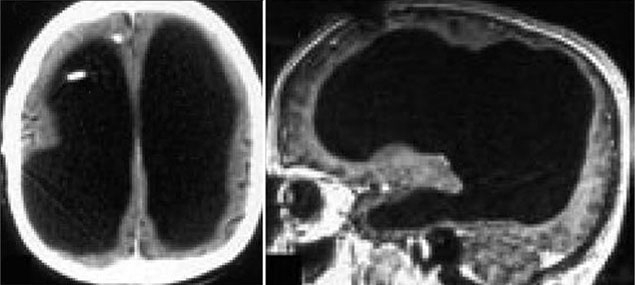

After the CT scan and magnetic resonance, the doctor was surprised to see that his ventricles were enlarged, while the brain, the gray matter and the white matter, did not.

Brain images of strange men with small brains that are almost impossible.

It is known that when he was 6 years old, this man had a brain fluid. According to doctors, this may be the reason he doesn't have a brain. But this omission did not hinder his development.